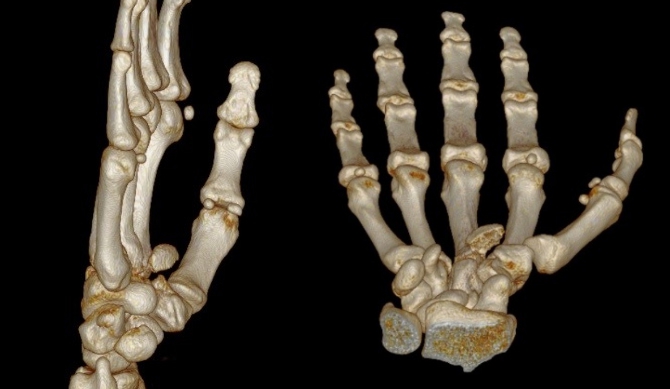

Fractura del cóndilo cubital de la base del 2do metacarpiano con desplazamiento a palmar. Presentación de un caso